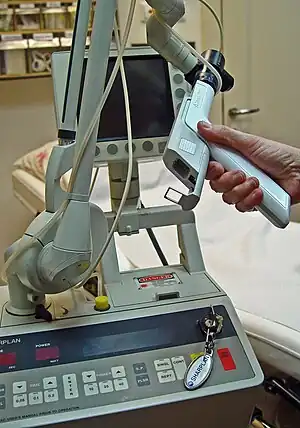

| Electrical cautery |  |

Electrical surgical cauterization utilizes electricity in either a mono-polar or bi-polar format to burn soft tissue and control bleeding.[12] |

|